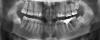

Layla Опубликовано 27 сентября, 2012 Поделиться Опубликовано 27 сентября, 2012 (изменено) Добрый день! Очень нужна консультация специалистов, т.к. я в полной растерянности. Так сложились обстоятельства, что процесс исправления прикуса я начала в другой стране и достаточно спонтанно.Мне 26, 5 лет. Была на консультации у 3 докторов, 2-ое из которых, не гляди на снимки с ходу сказали, что нужен аппарат RPE (в моем случае, как я поняла по фото, Хайрекс). 1 доктор советовал удалять. О хирургическом расширении никто из 3 не говорил.За 2 недели сделали аппарат и поставили почти 2 недели назад. Врач ничего толком не объяснила, ни планы лечения, ни возможные последствия, только сказала, что через пару дней я об аппарате забуду и что нужно раскручивать 3 раза в неделю.Я спросила, на сколько нужно расширить челюсть, она ответила -10 мм. Первые дни была сильная боль в области шестерок, на которых стоят кольца, жевать вообще не могла, да и до сих пор с трудом, челюсть не смыкается. Весь язык в ранах и не заживает , полоскания и сосательные таблетки от стоматита не помагают, слева верхние дуги врезаются в небо. результат -4 кг за неделю.Дикция ужасная, работа предполагает лекции на большие аудитории, не знаю , что делать. Пришлось самой начать изучать все в интернете.в итоге возникли вопросы по поводу адекватности лечения.Уважаемые специалисты, пожалуйста, посмотрите снимки , может вы сможете что-то порекомендовать.1. Нормально ли, что не попросили удалить 8-ки, хотя на нижней челюсти они в ужасном положении?2. Есть ли вероятность, что небный шов не разойдется и что делать в данном случае ? за почти 2 недели чувствую небольшое напряжение в переносице ( вроде как-то врач говорил, что искривлена) , щель между 1-ками не появляется.3. Какие могут быть негативные последствия расширения в моем возрасте?4. Можно ли в моем случае обойтись без удаления?5. Можно ли исправить прикус без хайрекса в моем случае или заменить его на что-то другое?6. Что делать с израненным языком, т.к. принимать пищу вообще не представляется возможным.7. И самое главное, как звучит мой диагноз?Родители просят название, а врач не сказала...Заранее огромное спасибо, очень жду ваших ответов и советов. Изменено 27 сентября, 2012 пользователем Layla Ссылка на комментарий

Force Опубликовано 30 сентября, 2012 Поделиться Опубликовано 30 сентября, 2012 34-36 - нормальное расстояние. В вашем случае экспансия может быть достигнута только с помощью брекет-системы. Расширение хайрексом чревато последствиями, три-четыре оборота назад обвчно делают. Рекомендую обсудить с вашим лечащим доктором. Диагноз ваш - бимаксилярная ретрузия, сужение зубоальвеолярных дуг, тесное положение зубов верхней и нижней челюстнй.Удаление восьмерок внизу критично. Ссылка на комментарий

Force Опубликовано 30 сентября, 2012 Поделиться Опубликовано 30 сентября, 2012 Цель хайрекса - расширение. Но скелетное. То есть разломить челюсть на две части по срединному небному шву. Суть в том, что а. Небный шов у взрослого человека закрыт, разорвать его сложно. Б. Челюсть состоит вообще из трех частей. (Но это просто к размышлению)При расширении хайрексом у взрослого пациента происходит выталкивание корней за пределы альвеолярного отростка. Сразу это не видно. Аукается позже. Более того, при нормальном поперечном размере между молярами расширение в области моляров вообще не нужно! Это же логично? А вот наклоны других зубов могут быть изменены с помощью более гуманных испособлений. Но тут зависит от уровня ортодонта. 1 Ссылка на комментарий